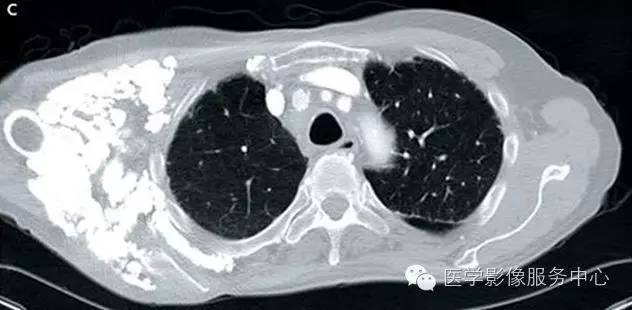

采取的治疗包括高剂量泼尼松、 静脉注射免疫球蛋白和青霉胺。尽管如此患者钙化依然在进展,逐渐导致手指、 手、 脚趾、 右胸和右大腿的功能障碍。外科松解手术虽可暂时缓解疼痛,但是不能控制钙化的进展。查体可见累及手掌以及所有手指未愈合溃疡的广泛软组织钙化,并伴有屈曲畸形。同样的广泛钙化也在X线片和胸部CT检查中被发现。

系统性硬化相关性间质性肺疾病的早期表现